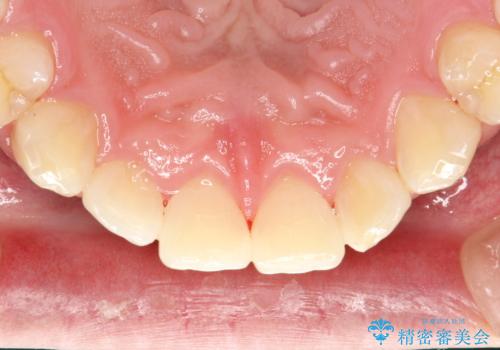

- 半年ぶりの来院で、全体的なチェックとクリーニング希望でした。PMTC(自費クリーニング)60分コースを行いました。

PMTCとは、プロフェッショナル(歯科衛生士)メカニカル(機械的)トゥース(歯)クリーニング(清掃)の略です。歯科医院にて、いろいろな機械・材料を使用し汚れを落とします。

磨き残しや、細菌は歯の表面がザラザラしている部分につきやすいです。そのためPMTCを定期的に繰り返すことで、歯の表面がツルツルの状態である期間が長くなるため、虫歯や歯周病予防につながります。